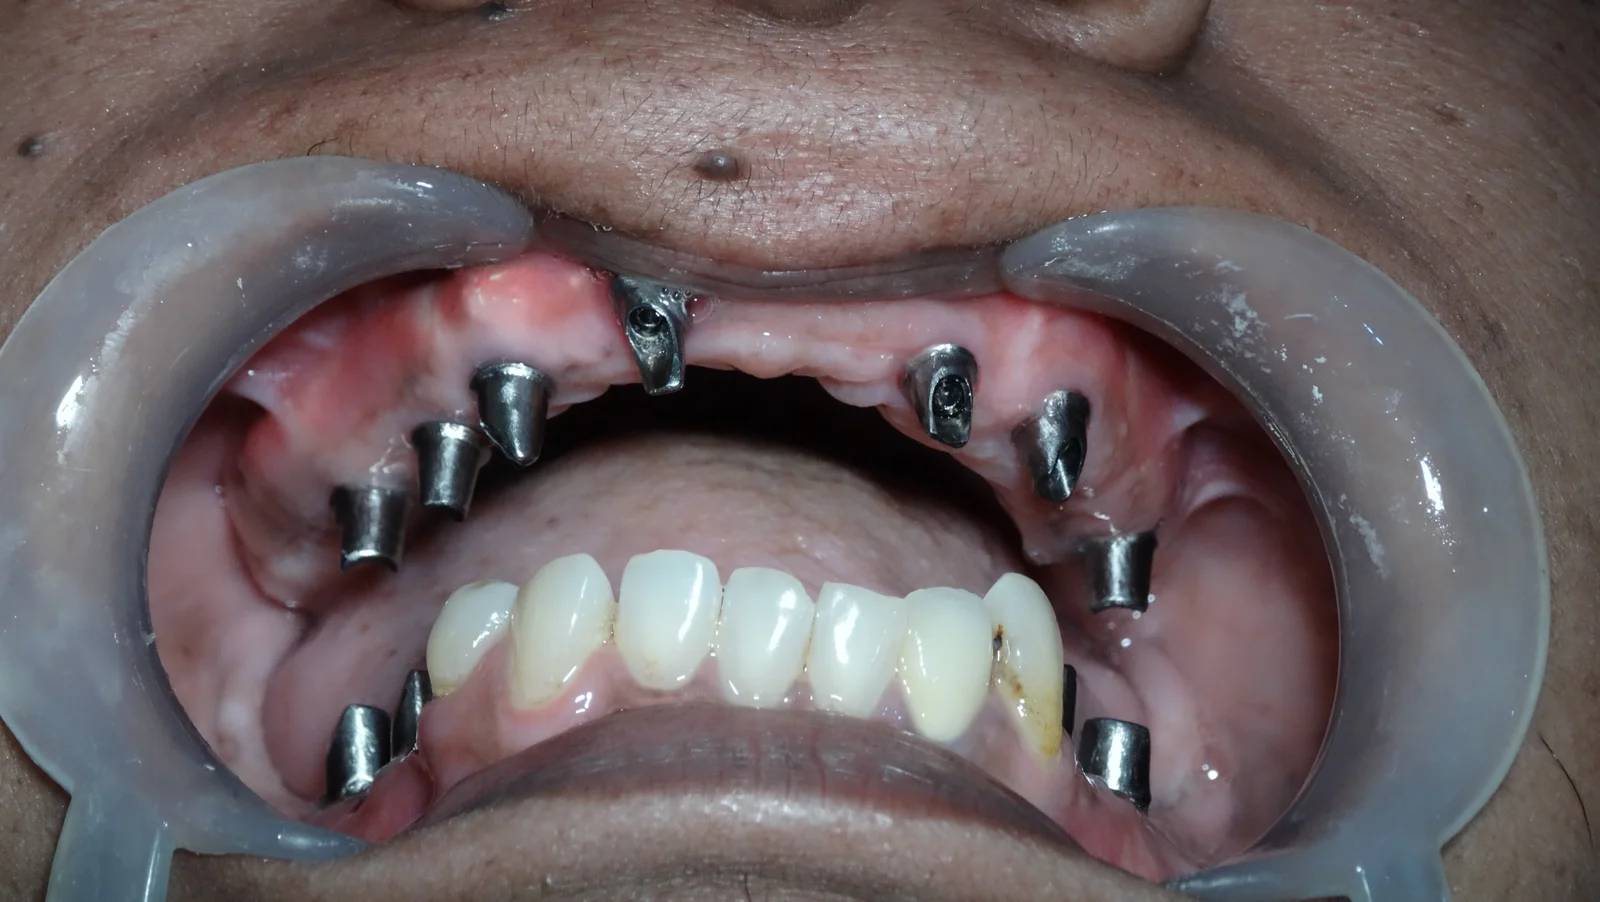

Clinical Case Progression

Full Mouth Rehabilitation

Implant Supported Fixed Teeth

Replacing all missing teeth with a permanent, fixed prosthesis that mimics the look, feel, and function of natural teeth. Explore our clinical transformations below.

Elite Implantology

Zygomatic Implants

A Specialist Job.

MDS Surgical Mastery

Zygomatic implants are an advanced implant technique where they are fixed to the Zygomatic arch for the upper jaw.

Eliminating the use of bone grafts, these implants allow you to get the prosthesis within 24 to 72 hours, unlike conventional implants that require months of waiting.